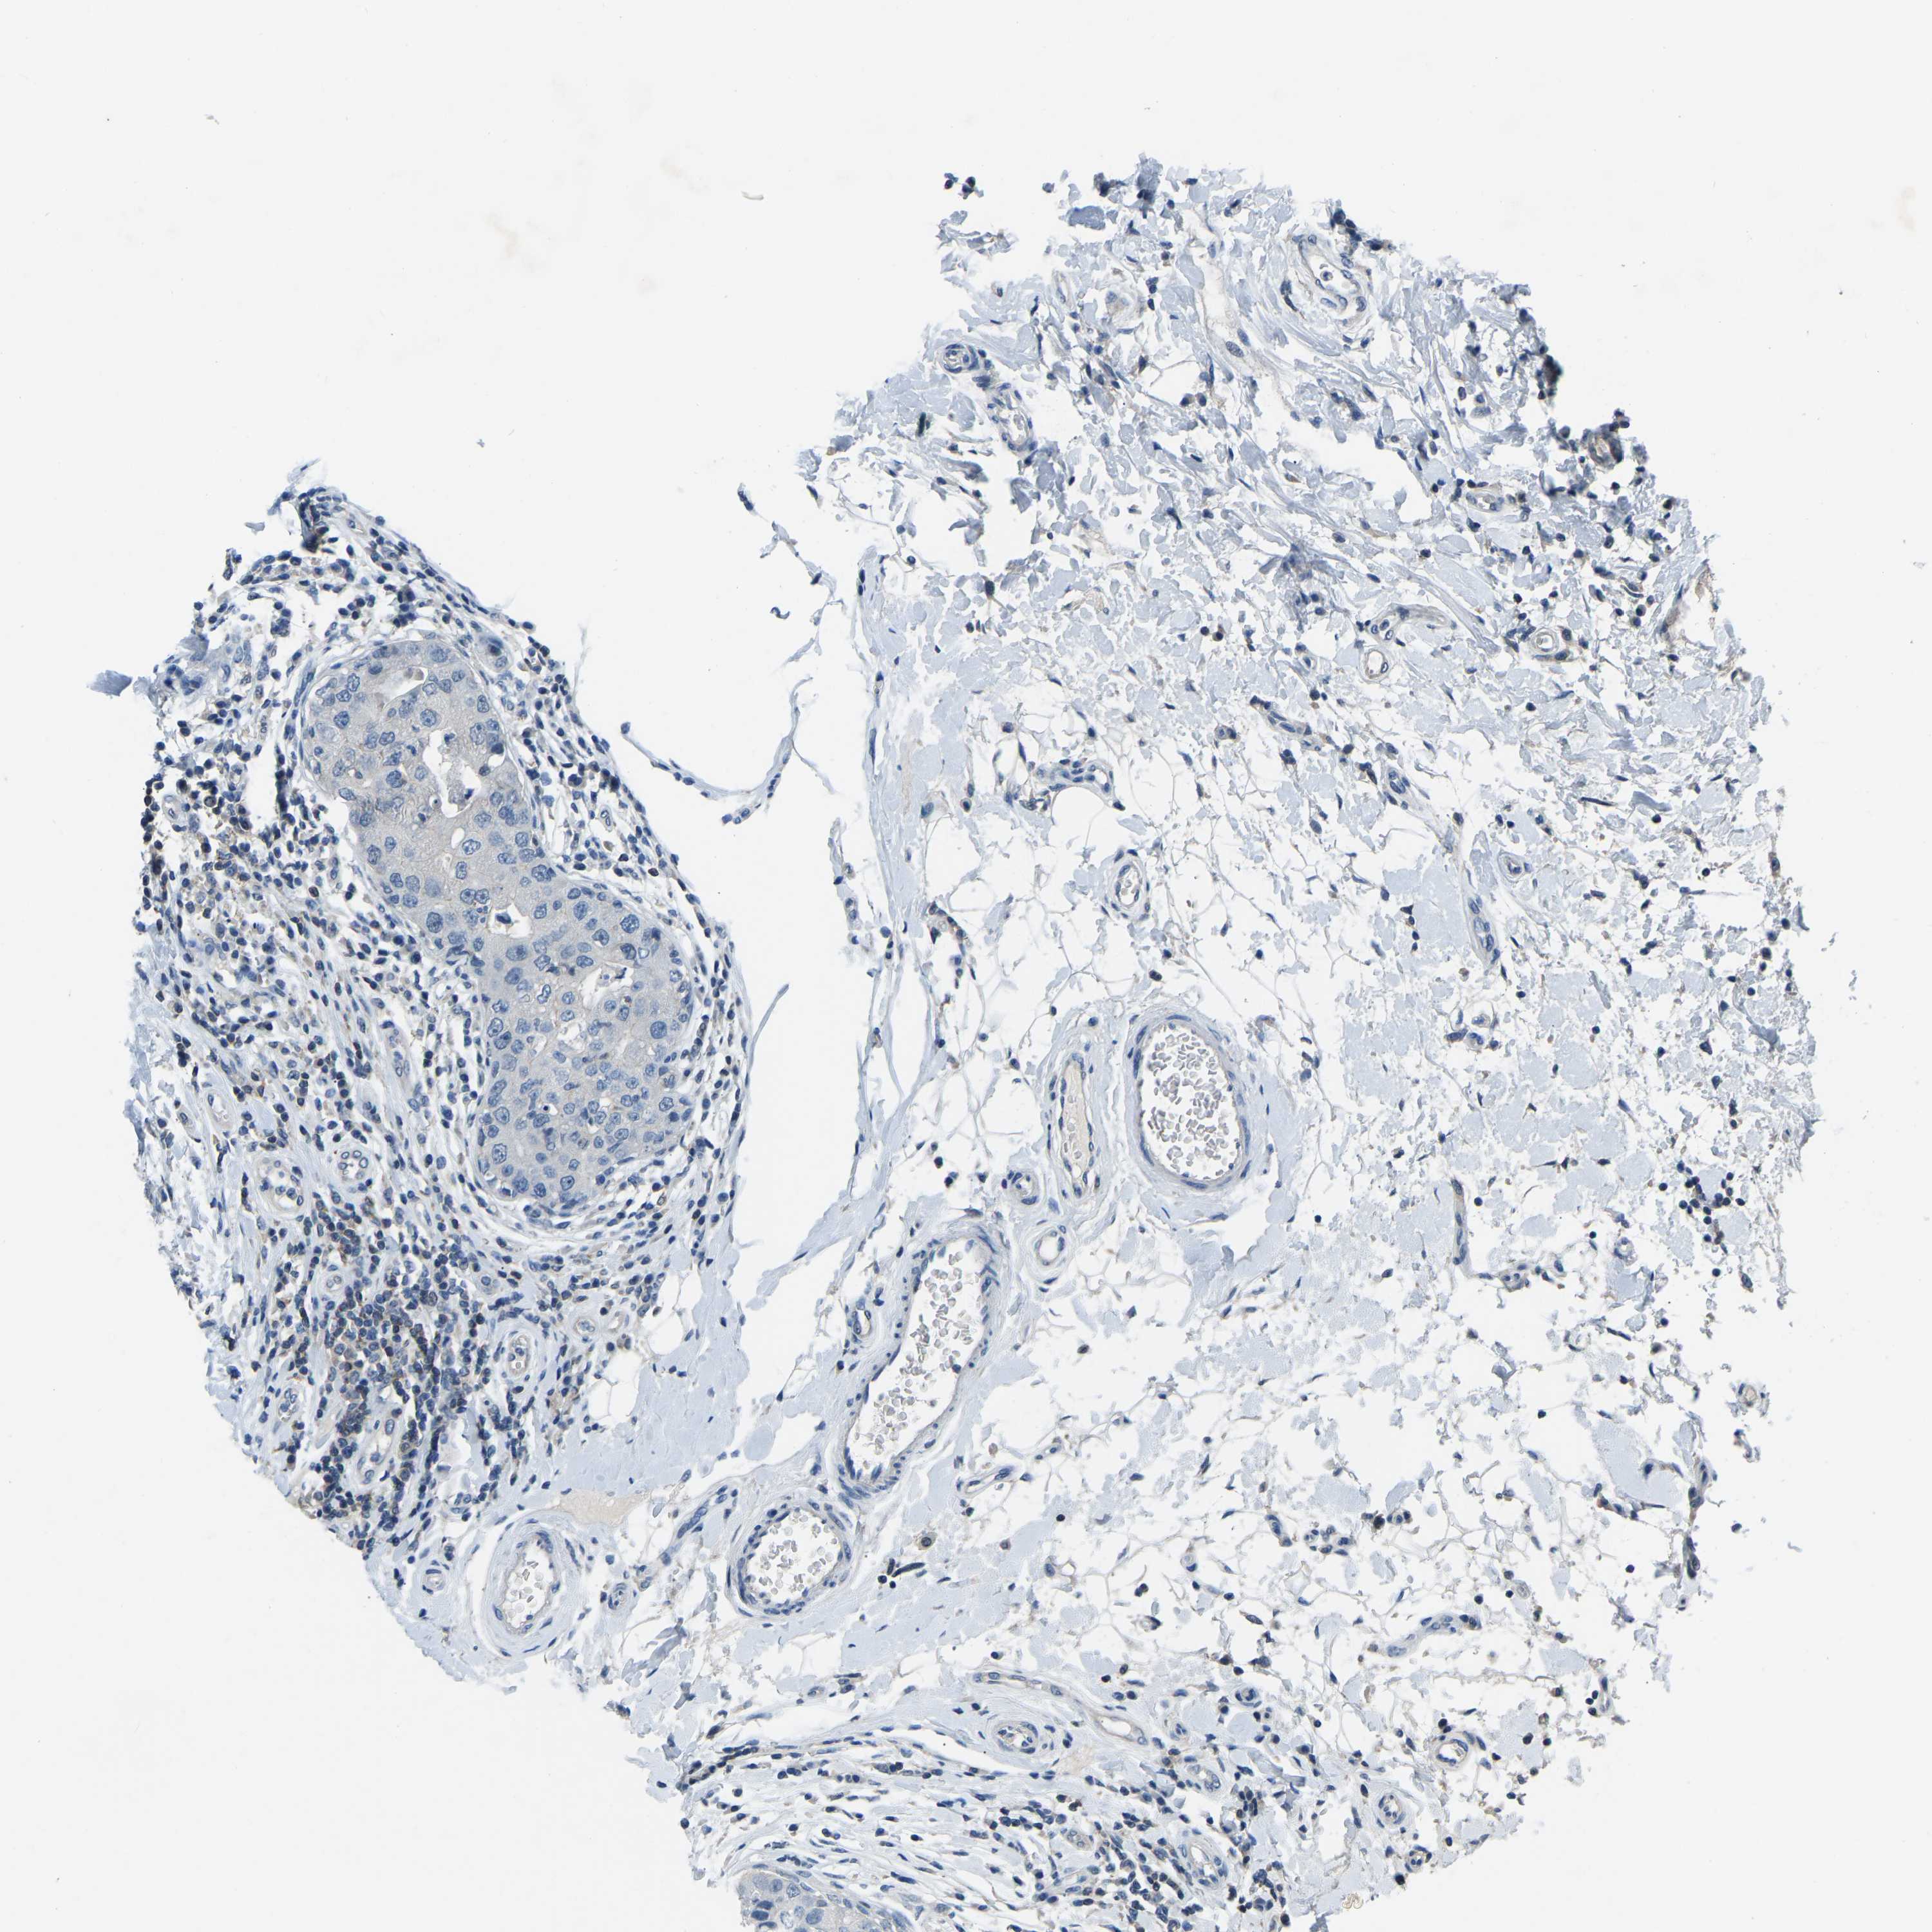

BRCA TCGA BRCA VALIDATION PROTEIN EXPRESSION